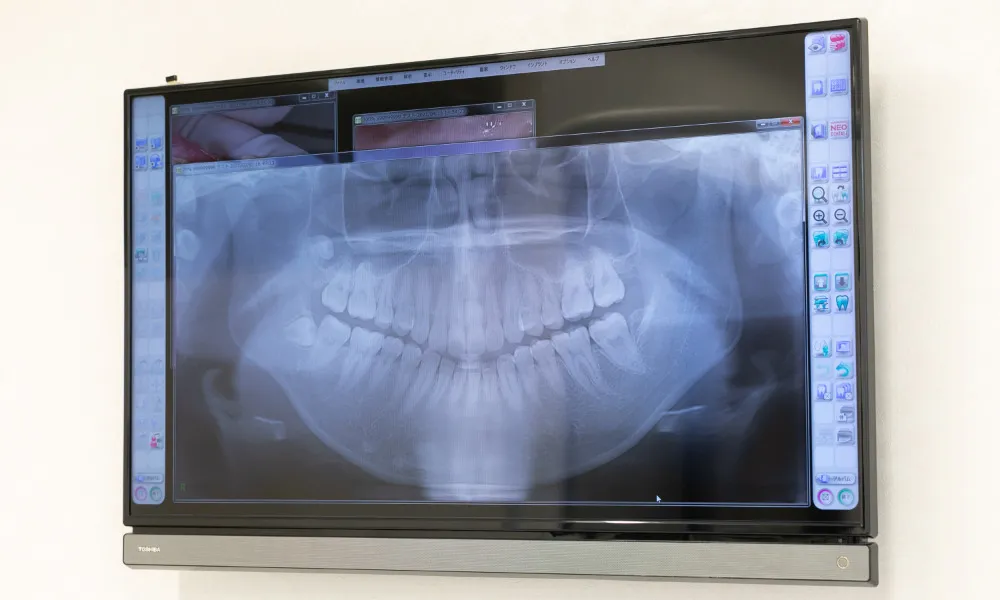

なお当院では、事前のレントゲン撮影や口腔内診査でむし歯の進行段階を把握し、適切かつ精密な治療を心がけております。またできるだけ痛みの少ない根管治療を行っておりますので痛みに弱い方や、歯科治療に恐怖心がある方も安心してご相談ください。